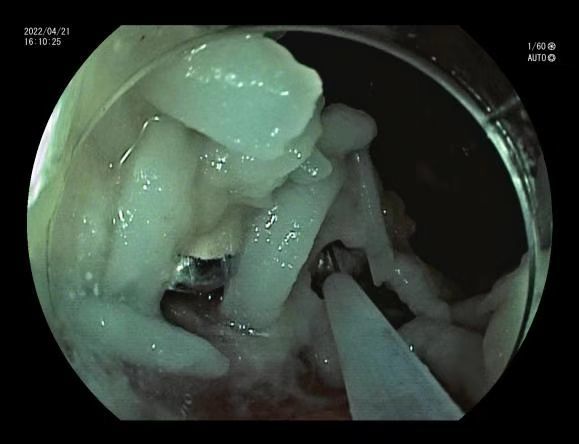

但取假牙并没有想象中的顺利,由于胃内仍存留大量未消化的食糜,内镜医生多次套取假牙失败,只能将董女士暂时收住入院。晚上9点,董女士再次接受内镜取物。这次胃内食糜较之前减少不少,内镜医生用活检钳仔细分离食物残渣后,用网兜顺利抓取假牙,小心翼翼地将它取了出来。假牙总算“重见天日”了!